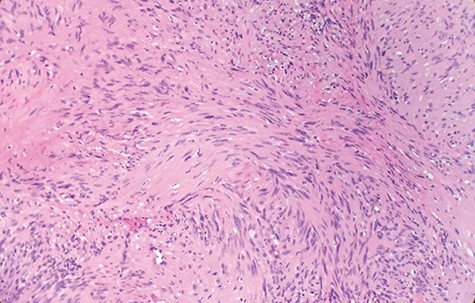

Macroscopically, the tumor appeared encapsulated, rubbery and pink-tan in color. Microscopic examination reveals that tumor composed of biphasic spindle hypercellular Antoni A areas and hypocellular Antoni B areas (Fig. 1). Higher magnification reveals that spindle tumor cells are narrow, elongate, wavy with tapered ends interspersed with collagen fibers (Fig. 2). Immunohistochemical staining revealed that most tumor cells reacted strongly for S-100 protein (Fig. 3). Combined with immunohistochemical profile, these histological features are diagnostic of benign schwannoma. Patient was discharged home on the same day as the operation. At the 1-month follow-up, he was symptom free, without any pain or sensory disturbances.

Immunohistochemical staining revealed that tumor cells are strongly positive for S-100 protein (×40).